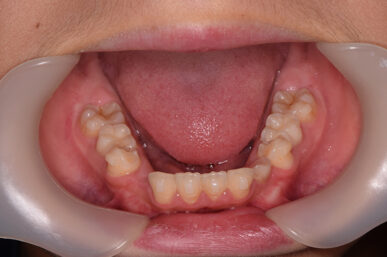

• Before

治療の開始が遅く、犬歯と奥歯の生え代わりが始まっていましたが、床矯正より治療スピードが早いアライナー矯正を使用して、犬歯のスペースをとても短期間に作ることができました。八重歯を防げましたので固定式の装置は必要なくなりました。永久歯がすべて生えるまでは予防歯科で歯の生え代わりと機能を管理します。